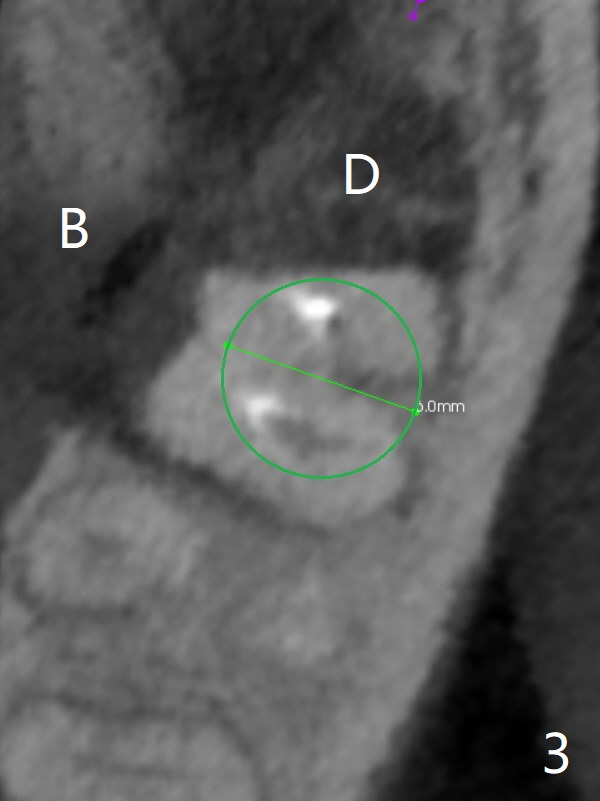

A 53-year-old man will return for #18 extraction and implant because of endo failure after the same treatment at #14 (Fig.1). It appears that the mesiolingual canal is missing for RCT (Fig.2 (coronal section at the mesial root)). Bony defect is buccodistal; try to place an implant as mesiolingual as possible (Fig.3 (axial section)). To reduce lingual (L) plate perforation and neuropathy (orange), the implant is expected to be 5-6x9 mm (Fig.4,5). Use 4 mm stopper from DIO Sinus Kit for osteotomy (Fig.1,4,5). If his vein is prominent, prepare PRF 1-2 tubes.